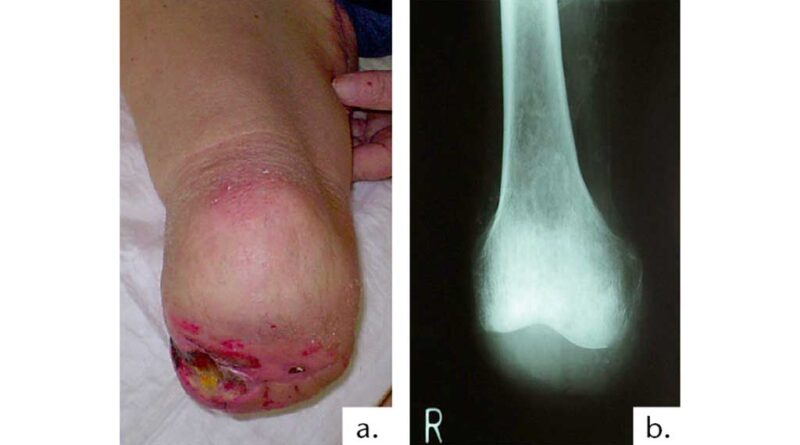

Eine Hautdehiszenz bei nicht spannungsfrei adaptierter Wundnarbe auch außerhalb der Belastungszone ist eine Behinderung für den Amputierten. Der Stumpf ist voll endbelastbar, aber die Haut retrahiert sich (Abb. 9).

Ein Dekubitus im Bereich der Femurkondylen durch postoperativ falsche Lagerung und zu enge Wickelung (Abb. 10) führt zu einer unnötigen prolongierten Rehabilitation eines an sich kurz nach der Amputation voll gehfähigen Patienten.